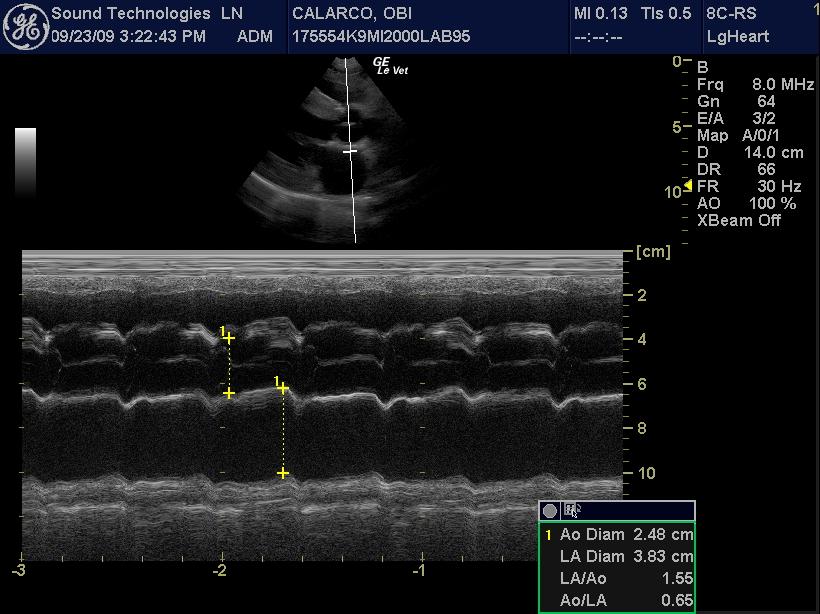

An 11-year-old MN Labrador retriever was prestented for excercise intolerance, lethargy, depression, vomiting and diarrhea. The physical exam was unremarkable other than a grade 2 left sided heart mumur at the heart base and irregular heart beat with pulse deficits. CBC, CHEM, UA, and acth stim were all normal.